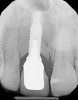

Fig 13. Case 2: Close-up retracted preoperative view of a patient who presented with a worn crown and post that had been removed and re-cemented several times.

Figure 13

Fig 14. Preoperative radiographic view of the worn post.

Figure 14

A patient presented with a worn crown and post that had been removed and re-cemented several times (Figure 13 and Figure 14). Among the approaches that could have been considered was an extensive procedure to include extraction, implant placement, bone grafting, and soft-tissue grafting simultaneously.